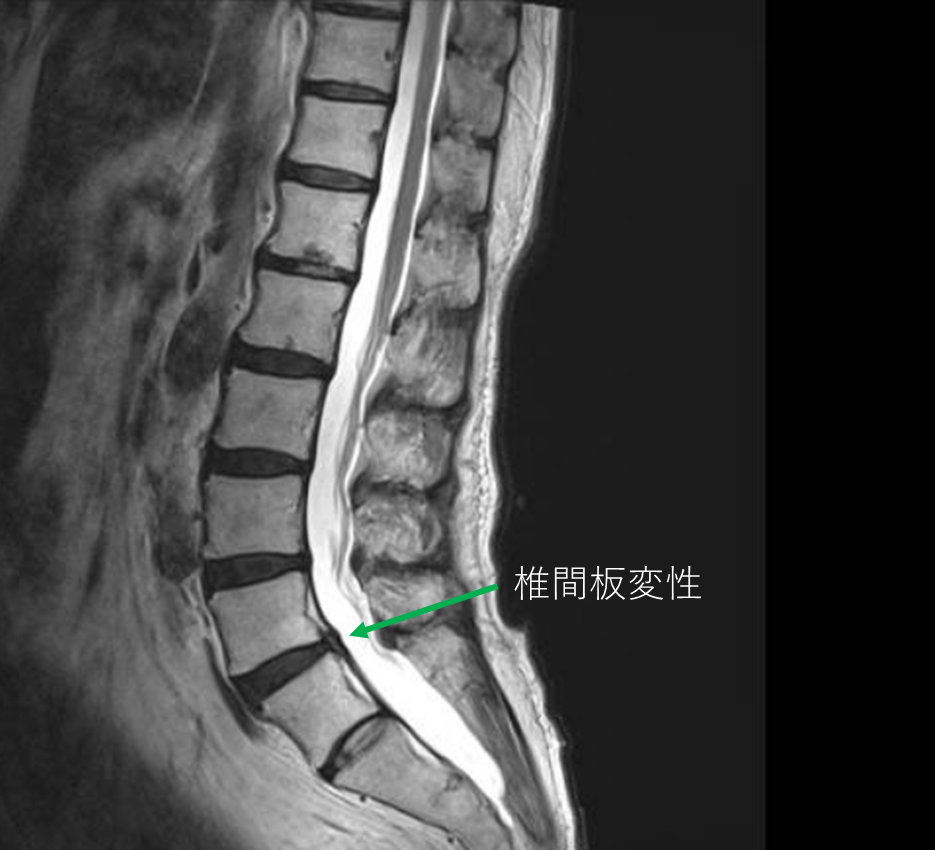

画像及び所見について

• L5/s-椎間板変性

以上の事が画像上認められます。

・L5/s-椎間板変性による右椎間孔狭窄を認め、主症状の原因の可能性がある

DiscoGelを入れた後の画像になります。